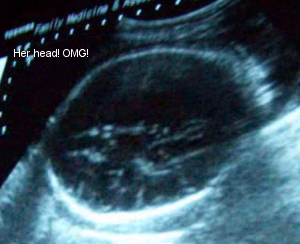

February 9th: I went in to the office in Mission since that’s where Dr. C. was today. I got an ultrasound done; everything’s looking great with the baby. Her head measured 36 weeks, so she’s right where she should be. Dr. C. did measurements and everything’s fine. Her head is firmly in my pelvis and quite low. I had a pelvic exam done and I’m not dilated or effaced yet. Dr. C. got the results for the GBS culture and I couldn’t believe it: I tested positive. He prescribed antibiotics, but my paranoid, hypochondriac self did research and I read you shouldn’t take antibiotics until labor or when the water breaks or the infection could come back once it clears. So now I’m wondering what to do with these pills. I need to call and be sure Dr. C. prescribed the right thing.

Sono Pic: